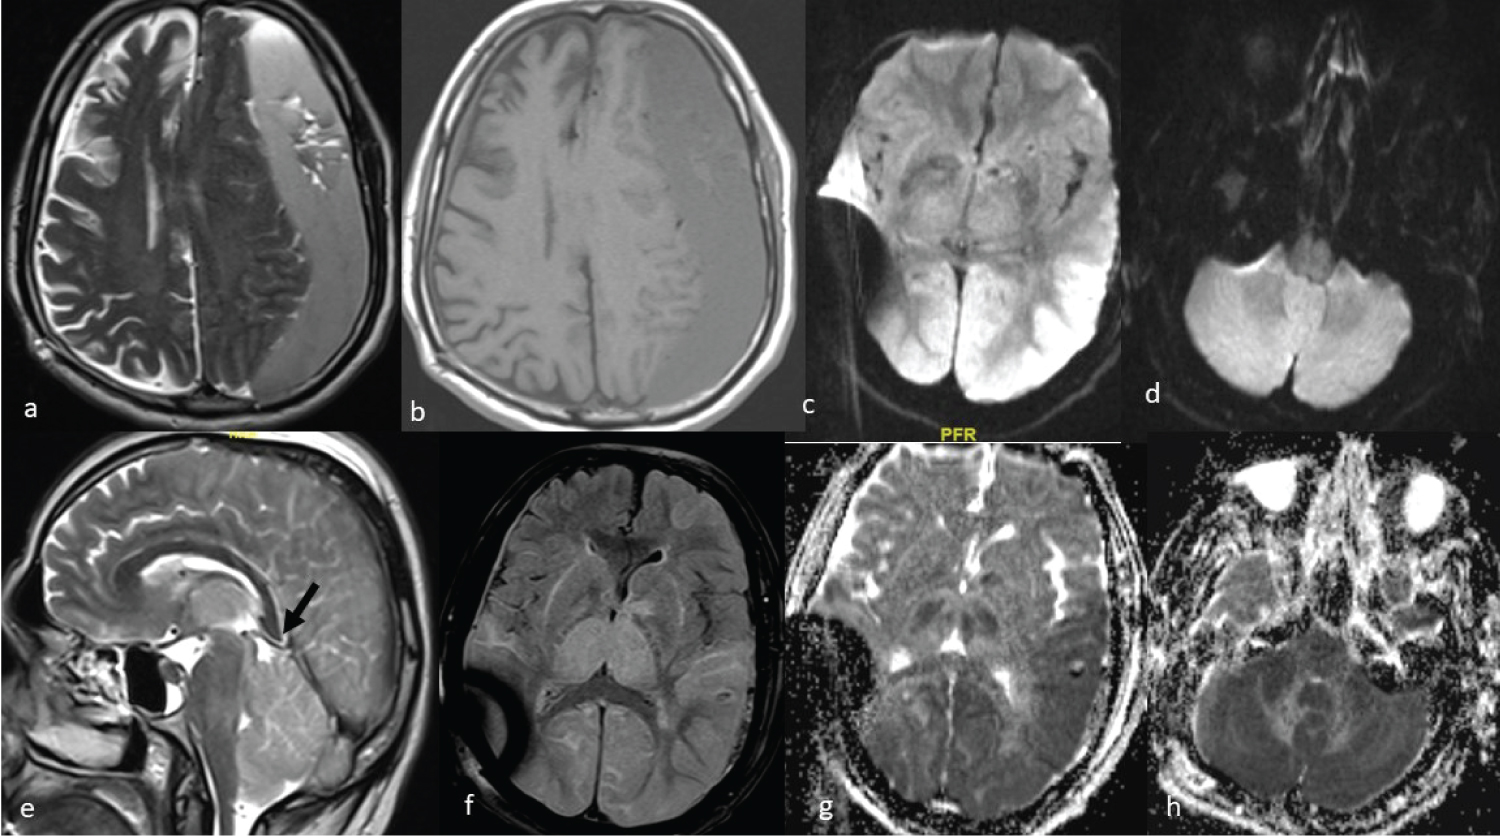

A 72-year-old known hypertensive male presented with frontal headache and weakness in right upper and lower limb for two days. On examination, the patient was fully conscious with normal vital parameters. Motor examination revealed right hemiparesis (power 3/5 in upper and lower limb). MRI brain with contrast (Figure 2a) showed a large subdural collection in left frontoparietal region causing significant mass effect on the left cerebral hemisphere and midline shift with effacement of the left lateral ventricle and underlying sulcal spaces. Thin subdural collection was also present along the right frontoparietal convexity with no mass effect. Blood investigations were normal. ECG showed sinus bradycardia with right bundle branch block and Echocardiography was within normal limits. Mannitol 100 ml intravenously three times a day and Injection levetiracetam 500 mg intravenously twice daily was started. He underwent left frontal and parietal burr hole evacuation of SDH under general anesthesia. The surgery was uneventful. Postoperatively, the patient had no spontaneous movements or reaction to painful stimuli although spontaneous respiration had returned. The Babinski sign was positive on both sides. Spontaneous eye opening was also present with preserved pupillary light reaction. NCCT head was done in operation theatre which did not show any obvious abnormality. The patient was shifted to ICU on ventilator with stable vitals. Electroencephalography was done to rule out non-convulsive seizures. Three hours after surgery, GCS of the patient was still E4VTM2 so MRI brain (Figure 2b, Figure 2c and Figure 2d) was done which revealed bilateral thalamic and basal ganglia hyperintensities, with no major diffusion restriction. No evidence of vascular abnormality was seen on MR angiography of brain and neck vessels. As no episode of intraoperative hypotension or hypoxia had occurred, based on clinical and radiological findings, acute intracranial hypotension was suspected. The patient was managed with Trendelenburg position and intravenous hydration. There was one episode of generalized tonic clonic seizure which was terminated with Injection Midazolam 2 mg intravenously and dose of Injection Levetiracetam was increased to 1 g intravenously two times a day. Repeat NCCT head was done on POD 1 which revealed diffuse hypodensities involving bilateral thalami and capsular ganglionic regions with focal area of hemorrhage in the left thalamus. The patient regained consciousness five days after the surgery. He was extubated two days later. Post extubation, GCS of patient was E4V2M6. Repeat MRI (Figure 2e and Figure 2f) done on POD 9 showed reduction in oedema in bilateral gangliothalamic regions. Due to a poor cough reflex, he was tracheostomized and discharged. He was decannulated two months later and had a Glasgow Outcome Score of 5 at that time.

Figure 2: T2W MRI image (a) showing large left frontoparietal subdural hematoma. Postoperative FLAIR MRI image (b) show signal change and swelling in bilateral basal ganglia and thalamus, however only small focusses of diffusion restriction are seen (d), suggesting reversible swelling. Sagittal T2W image (c) shows vein of Galen compressed by splenium with increased angulation at vein and straight sinus junction Follow up MRI (e&f) after 9 days shows reversal of thalamic and ganglionic swelling with visualized Vein of Galen.

MRI: Magnetic Resonance Imaging; T2W: T2 Weighted. View Figure 2